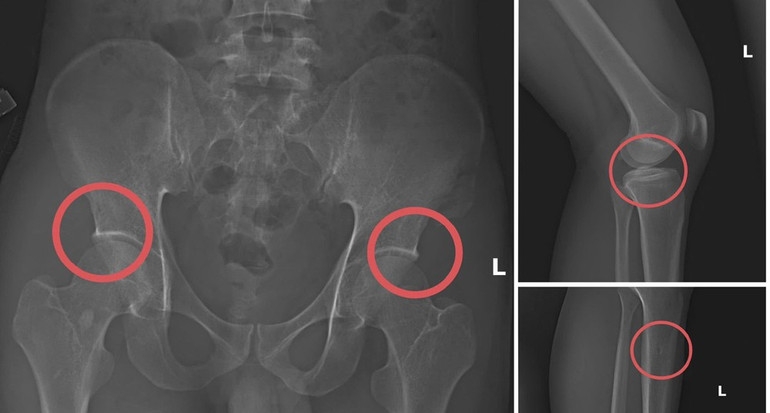

Theo Công an tỉnh Phú Thọ, đường dây trục lợi bảo hiểm bằng thủ đoạn tự đục vỡ xương khớp nhằm tạo thương tích giả do Tạ Minh Châu (SN 1996), nguyên cán bộ Trung tâm Y tế huyện Cẩm Khê cầm đầu.

Lợi dụng thời gian dài công tác trong ngành và am hiểu cấu trúc xương, khớp, Châu đã xây dựng quy trình trục lợi theo chuỗi khép kín gồm: Vận động người mua bảo hiểm nhân thọ, trực tiếp gây thương tích bằng thuốc mê và các dụng cụ tác động lực, sau đó dựng hiện trường giả để hợp thức hóa hồ sơ điều trị.

Đáng chú ý, Châu trực tiếp thực hiện hành vi tiêm thuốc mê rồi dùng kim tiêm, búa để tác động vào xương người mua bảo hiểm, tạo nên các vết vỡ xương tương tự tai nạn thật. Khi thương tích đã tạo xong, Châu tiếp tục hướng dẫn các đối tượng dựng hiện trường giả như điện giật ngã, trượt chân ngã suối nhằm hợp thức hóa bệnh án và hoàn thiện hồ sơ yêu cầu chi trả.